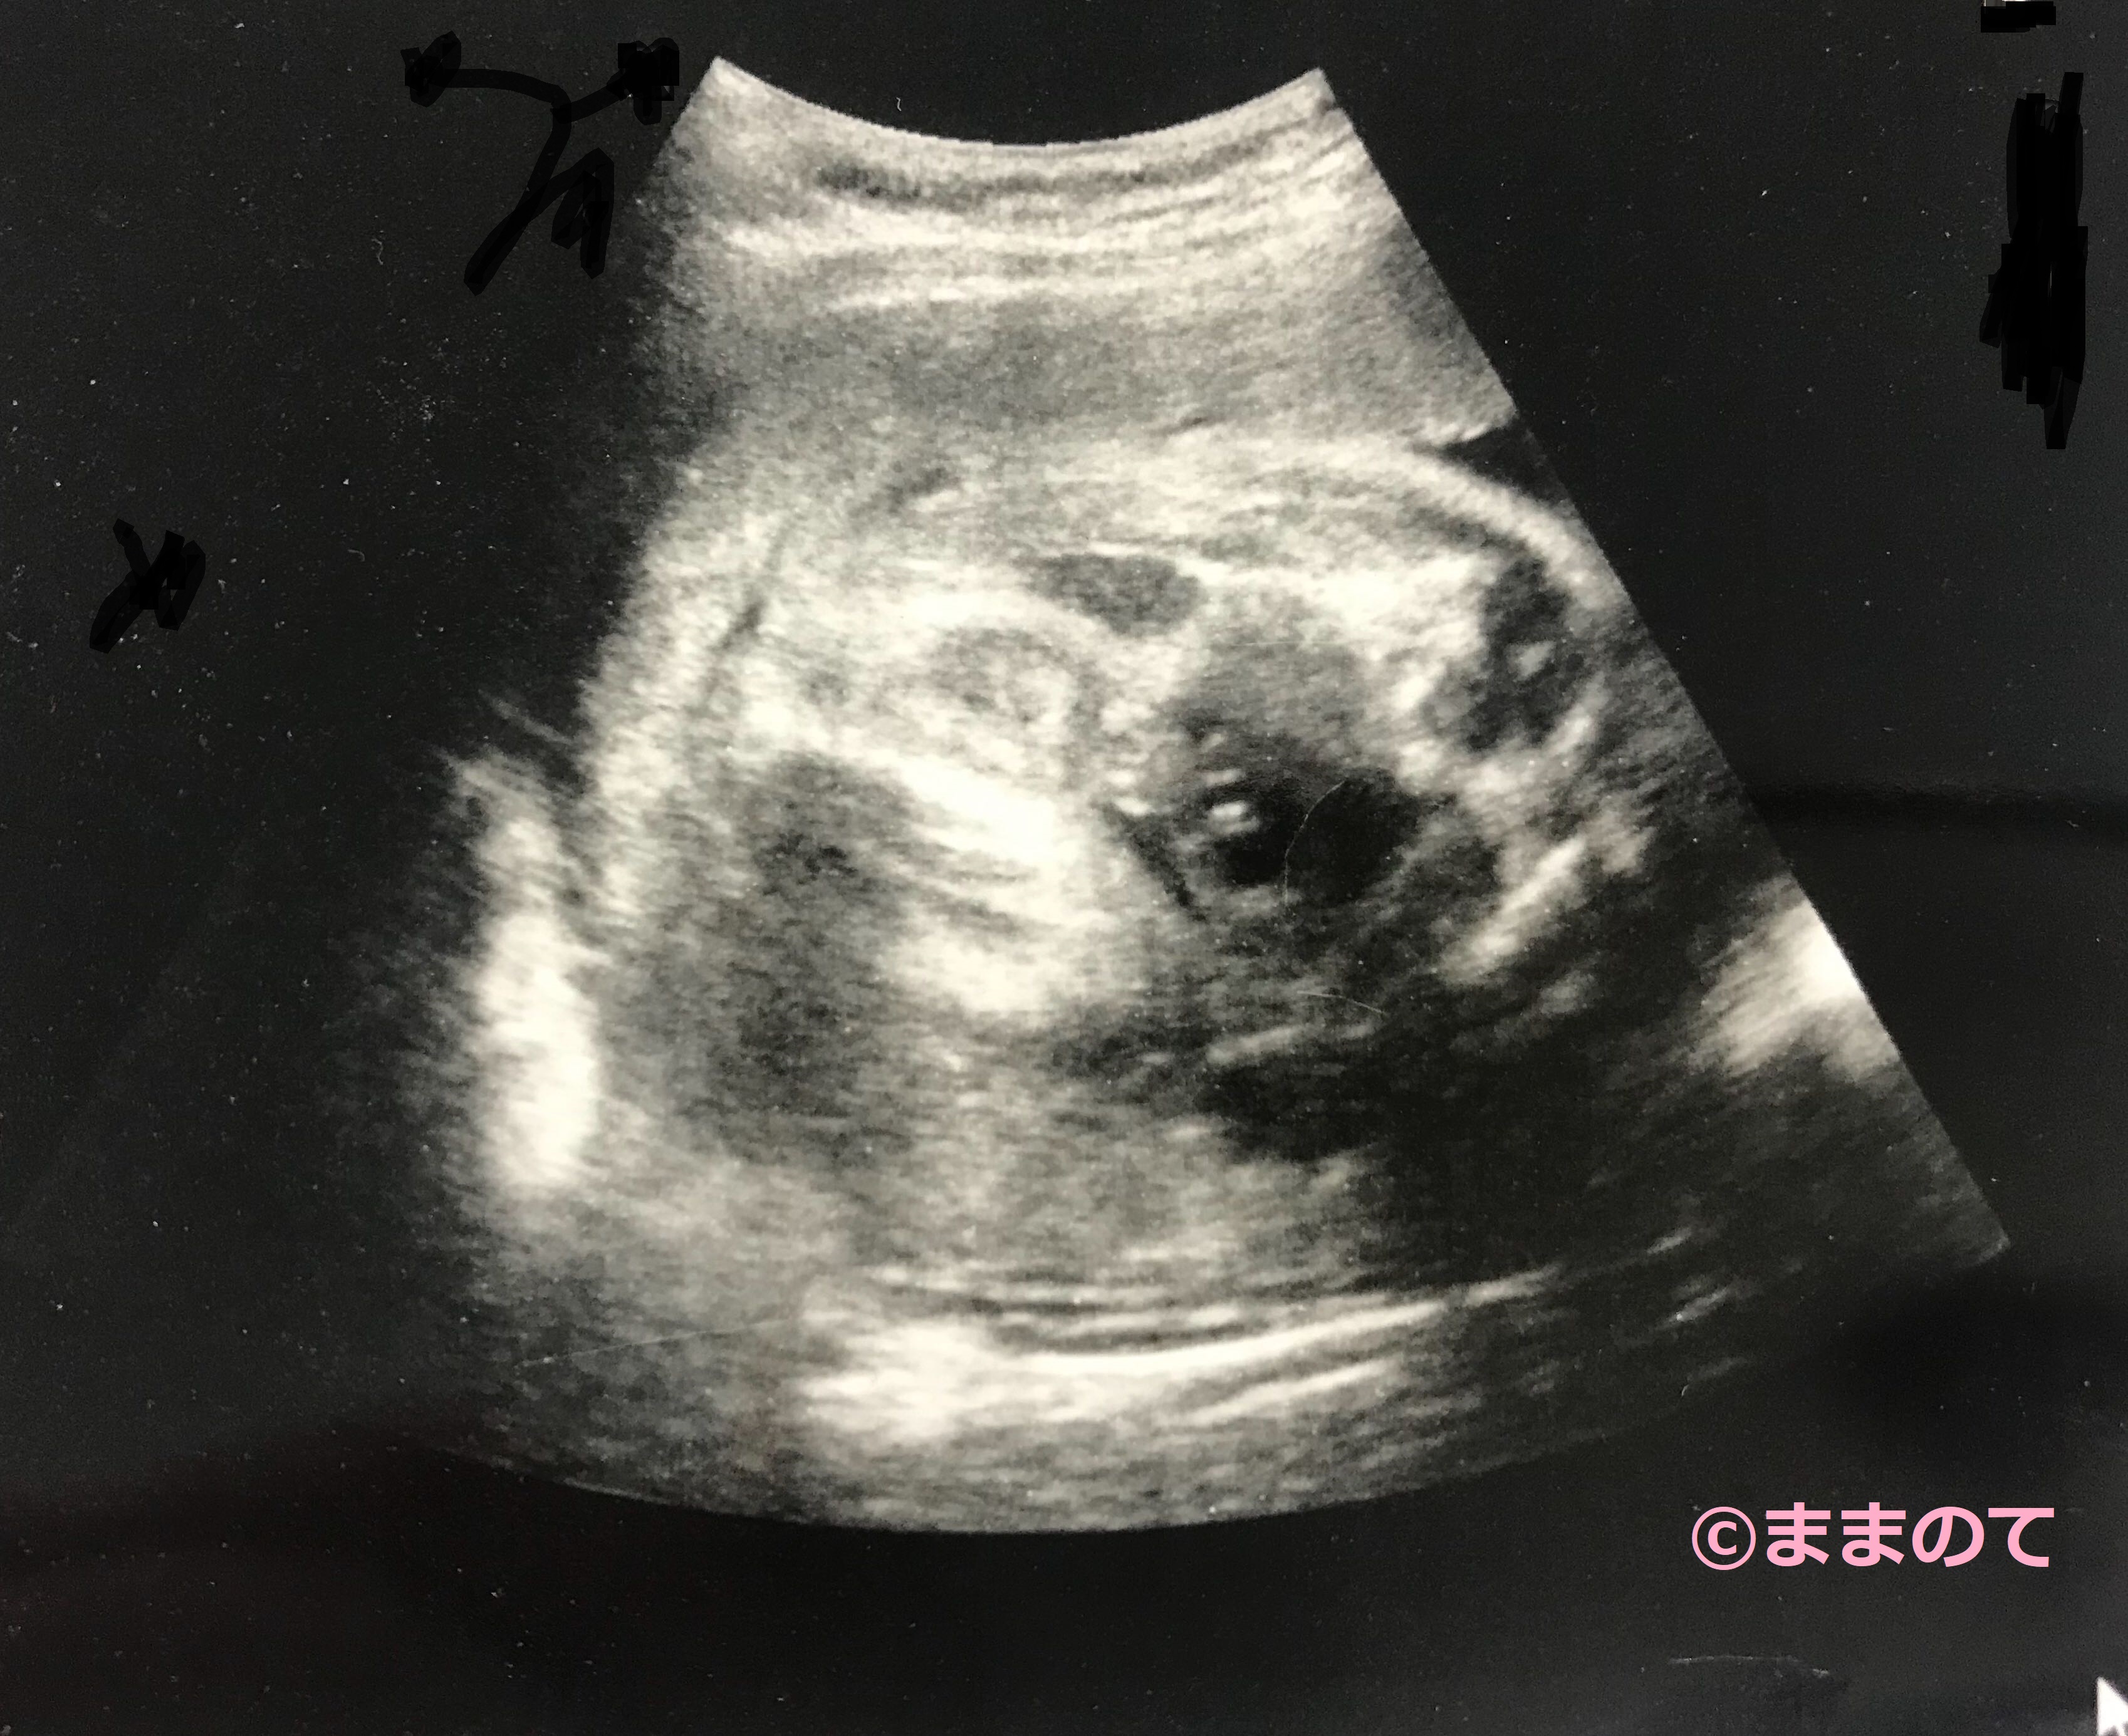

妊娠29週の赤ちゃんのエコー画像